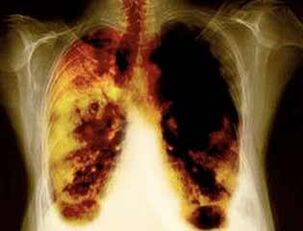

- Reducerea riscului de a dezvolta cancer pulmonar și multe alte tipuri de cancer.

- Reducerea riscului de a dezvolta anumite boli pulmonare (de exemplu, boli pulmonare obstructive cronice).

- După 1-9 luni, tuse și lipsa respirației au loc: cilia (părul mic) încep să trateze mucusul în mod normal, curățând plămânii și reducând riscul de infecție.

- La 10 ani de la încetarea fumatului cu 40%, probabilitatea cancerului pulmonar scade cu 40%.